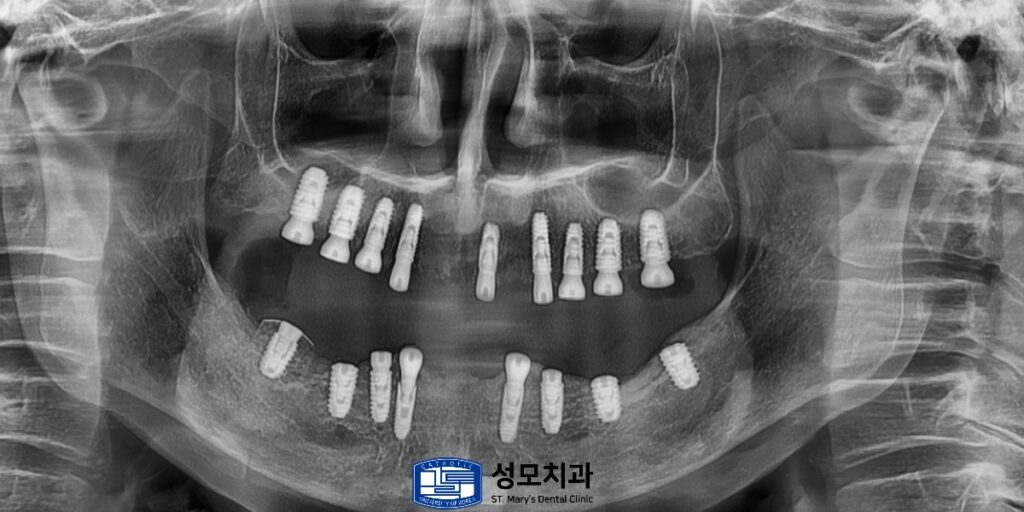

평면적인 X-ray를 촬영해 보아도

뼈가 확보된 것을 볼 수 있습니다.

모든 식립을 마무리한 뒤의 전체 x-ray 사진입니다.

식사를 할 때 힘이 많이 가해지는 어금니 부위는

임플란트 개수를 가능한 만큼 식립하였고

상대적으로 힘이 덜 들어가야 하는 앞니는

필요한 개수만 식립하였습니다.